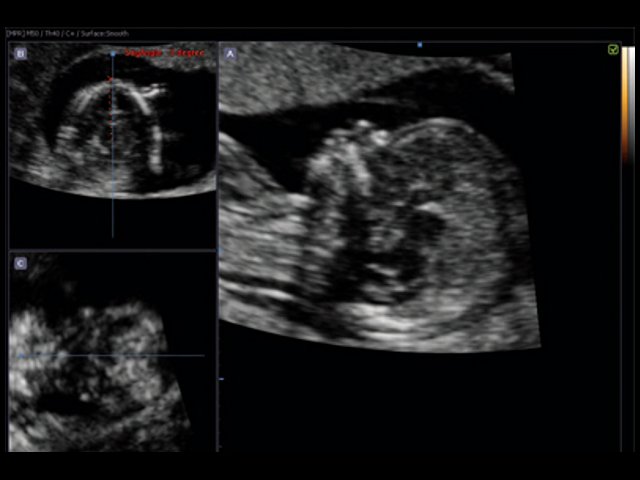

Volume NT - автоматический расчет ТВП

Volume NT™ (Nuchal Translucency - воротниковое пространство) - технология, позволяющая автоматически находить в массиве данных трехмерной эхограммы истинную срединно-сагиттальную плоскость для автоматического измерения толщины воротникового пространства (ТВП) и последующей оценки риска развития генетических врожденных аномалий плода.

Исходные данные для автоматического расчета ТВП.

Анатомические ориентиры на изображении плода в срединно-сагиттальной плоскости:

- Наличие эхогенного кончика носа и треугольная форма неба, расположенных впереди.

- Анэхогенный промежуточный мозг в центре и шейная складка, расположенная сзади.

- Отсутствие на изображении верхней челюсти, которая соединяется со скуловой костью.

Автоматическое обнаружение срединно-сагиттальной плоскости.

После того как изображение плода в истинной срединно-сагиттальной плоскости выведено на экран, пользователь может определить область воротникового пространства и автоматически измерить его толщину. Такой подход помогает избежать ошибки отклонения от плоскости, при котором не визуализируется кончик носа, но видна верхняя челюсть в месте ее сочленения со скуловой костью.

Автоматическое измерение ТВП.

Измерение ТВП, которое отображается на экране, является максимальным значением ВП, обнаруженным в зоне интереса, этот результат, автоматически заносится в отчет.